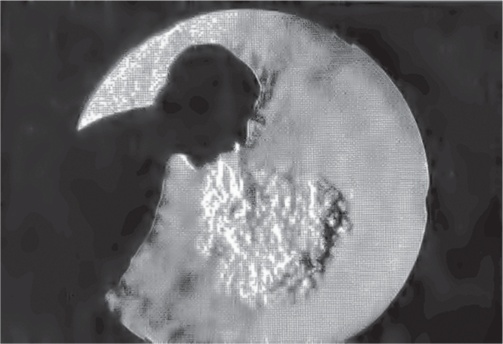

Ключ дала картинка, иллюстрирующая статью Грейди. Как-то, просматривая The New England Journal of Medicine, она наткнулась на статью под названием «Кашель и аэрозоли» (Coughing and Aerosols). Увидев ее, она поняла, что исследование – отличная основа статьи в Times. Некоторые части статьи были слишком специальными и содержали обсуждение заразности, аэрозолей и карты скорости. Но над всем располагалось простое изображение, которое и привело Грейди к решению написать статью.

Иллюстрация к книге — Заразительный. Психология сарафанного радио. Как продукты и идеи становятся популярными [i_005.jpg]